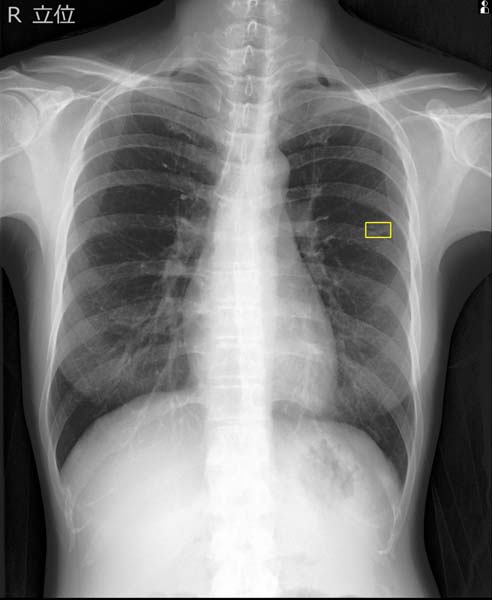

EIRL Chest Nodule(エイル・チェスト・ノジュール)検出画面(エルピクセル提供)